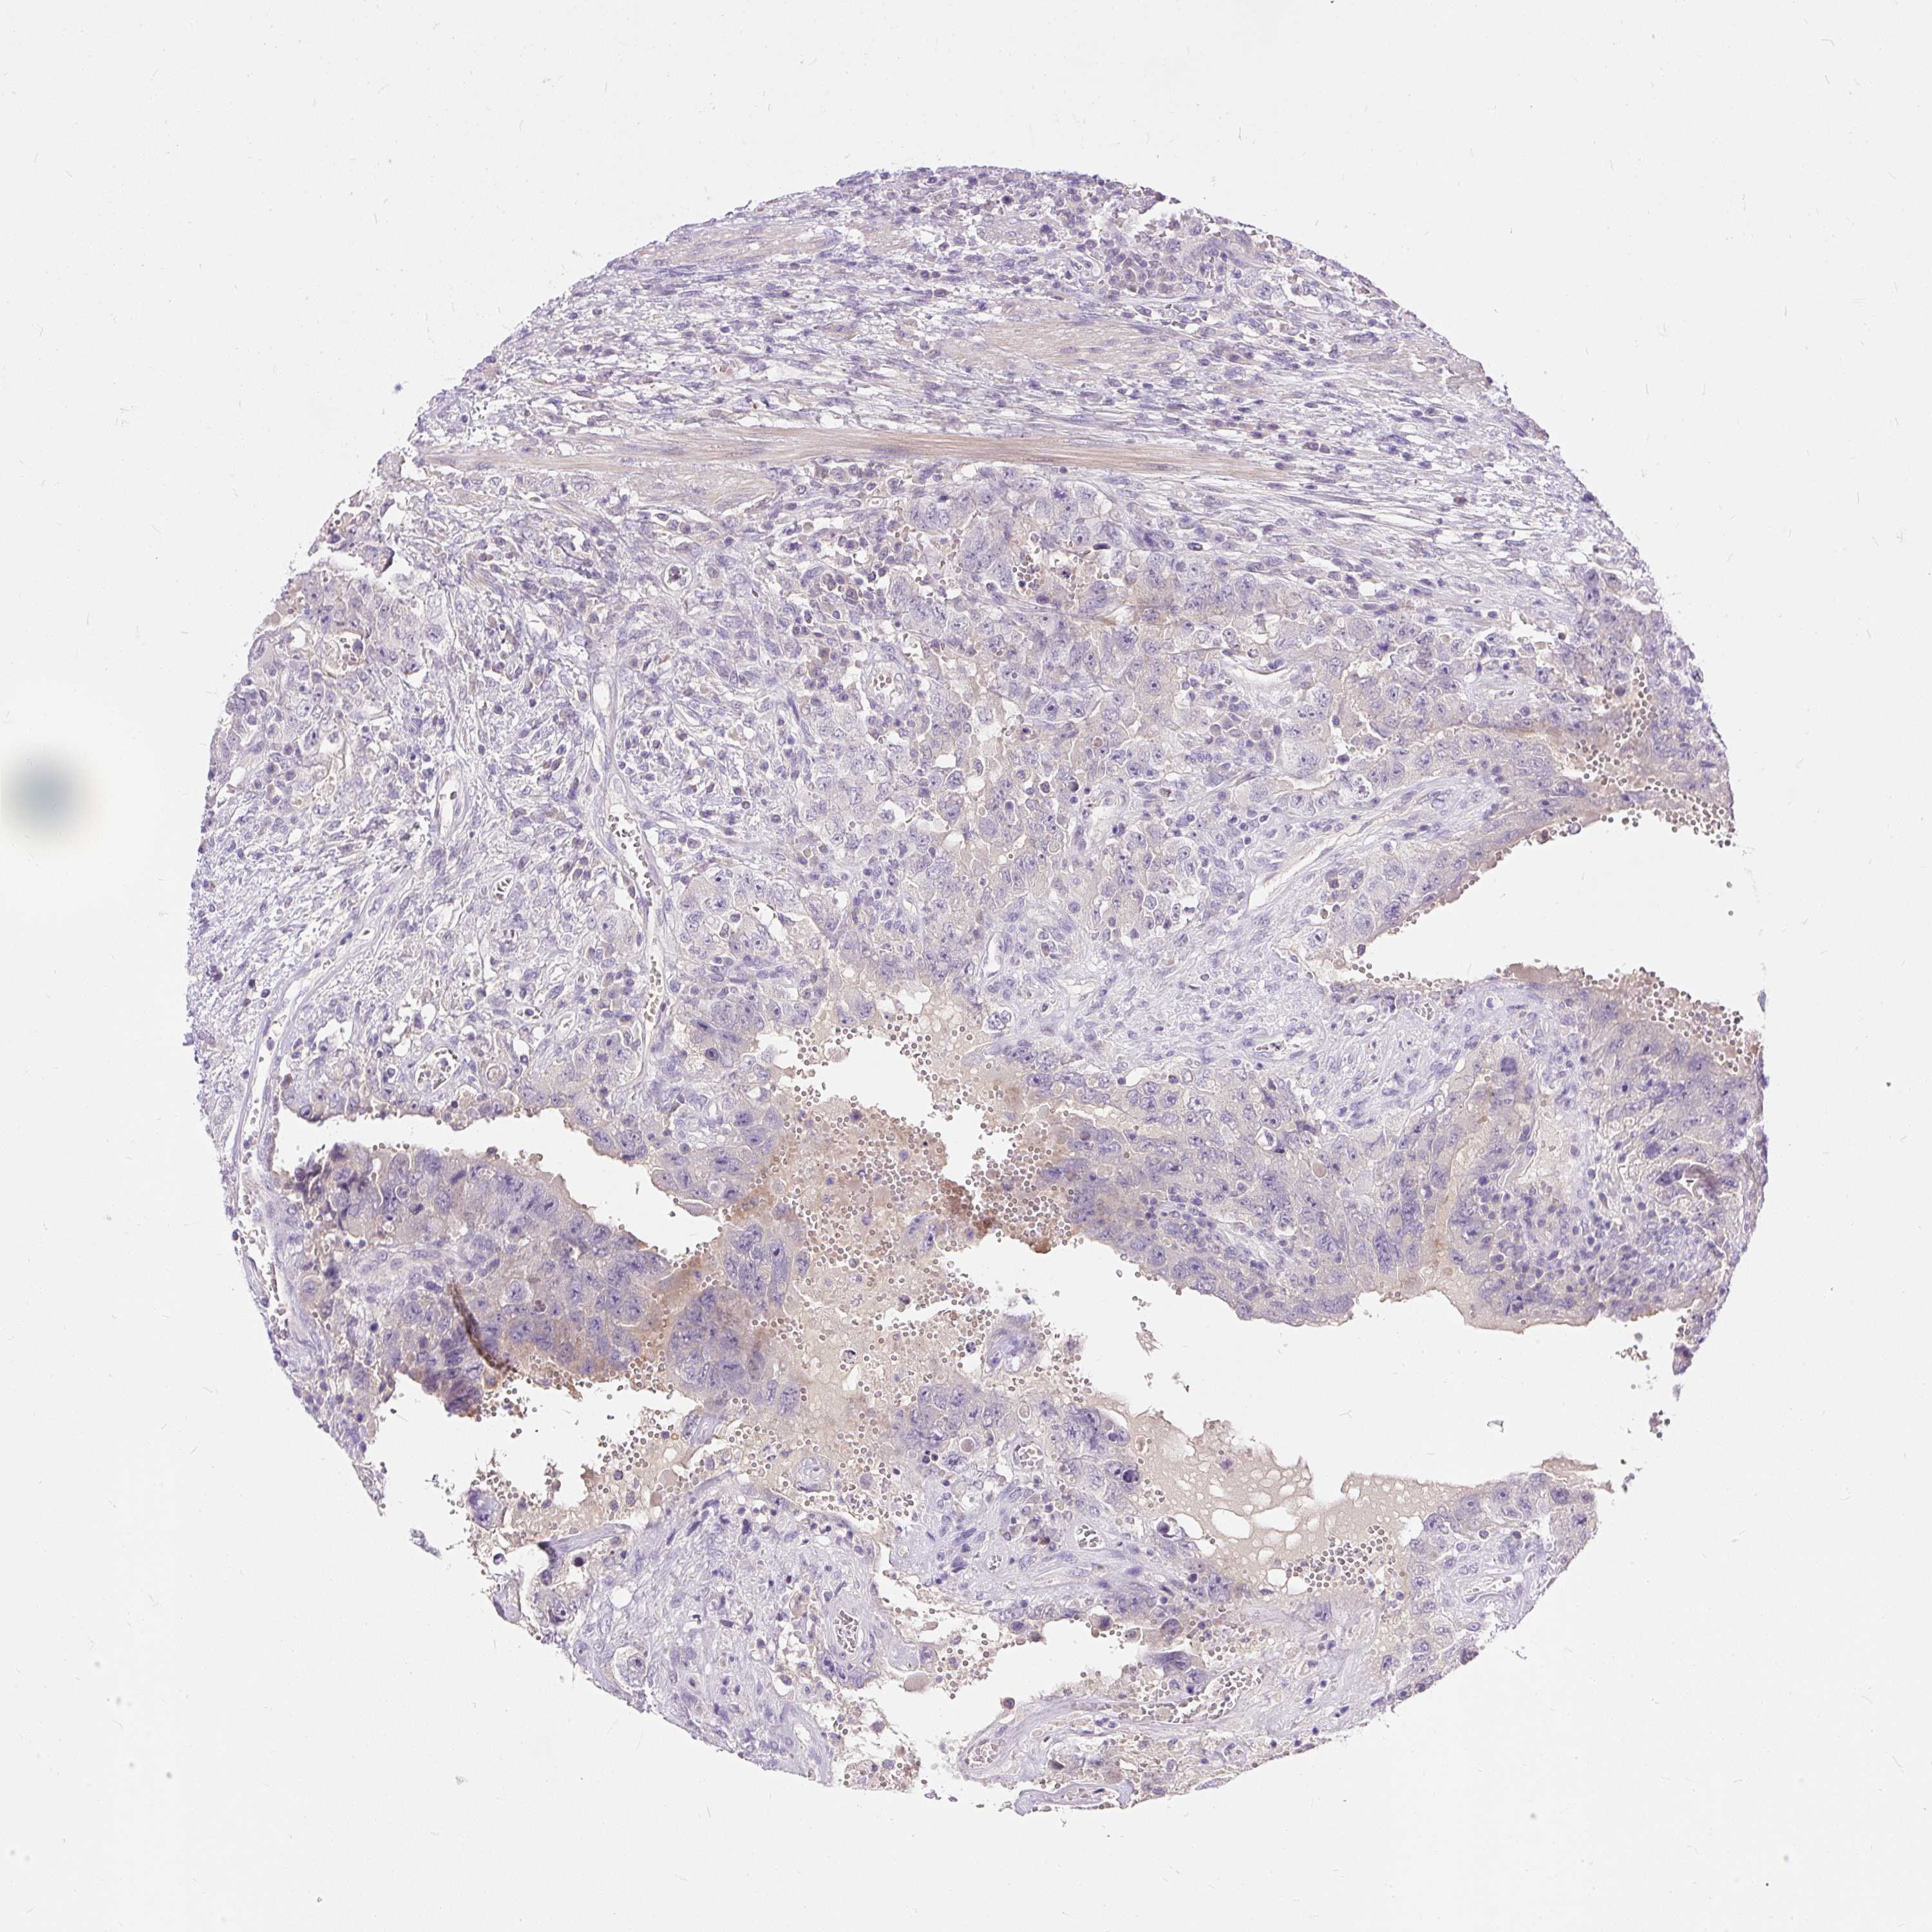

TESTIS CANCER - Protein expressioni

A mouse-over function shows sample information and annotation data. Click on an image to view it in a full screen mode. Samples can be filtered based on level of antibody staining by selecting one or several of the following categories: high, medium, low and not detected. The assay and annotation is described here.

Note that samples used for immunohistochemistry by the Human Protein Atlas do not correspond to samples in the TCGA dataset.

Antibody stainingi

Antibody staining in the annotated cell types in the current human tissue is reported as not detected, low, medium, or high, based on conventional immunohistochemistry profiling in selected tissues. This score is based on the combination of the staining intensity and fraction of stained cells.

Each image is clickable and will lead to virtual microscopy that enables deeper exploration of all samples and also displays staining intensity scores, fraction scores and subcellular localization as well as patient and tissue information for each sample.

Antibody HPA053598

Staining

High

Medium

Low

Not detected

Intensity

Strong

Moderate

Weak

Negative

Quantity

>75%

75%-25%

<25%

None

Location

Nuclear

Cytoplasmic/membranous

Cytoplasmic/membranous,nuclear

Carcinoma, Embryonal, NOS

Seminoma, NOS

Urothelial carcinoma, High grade